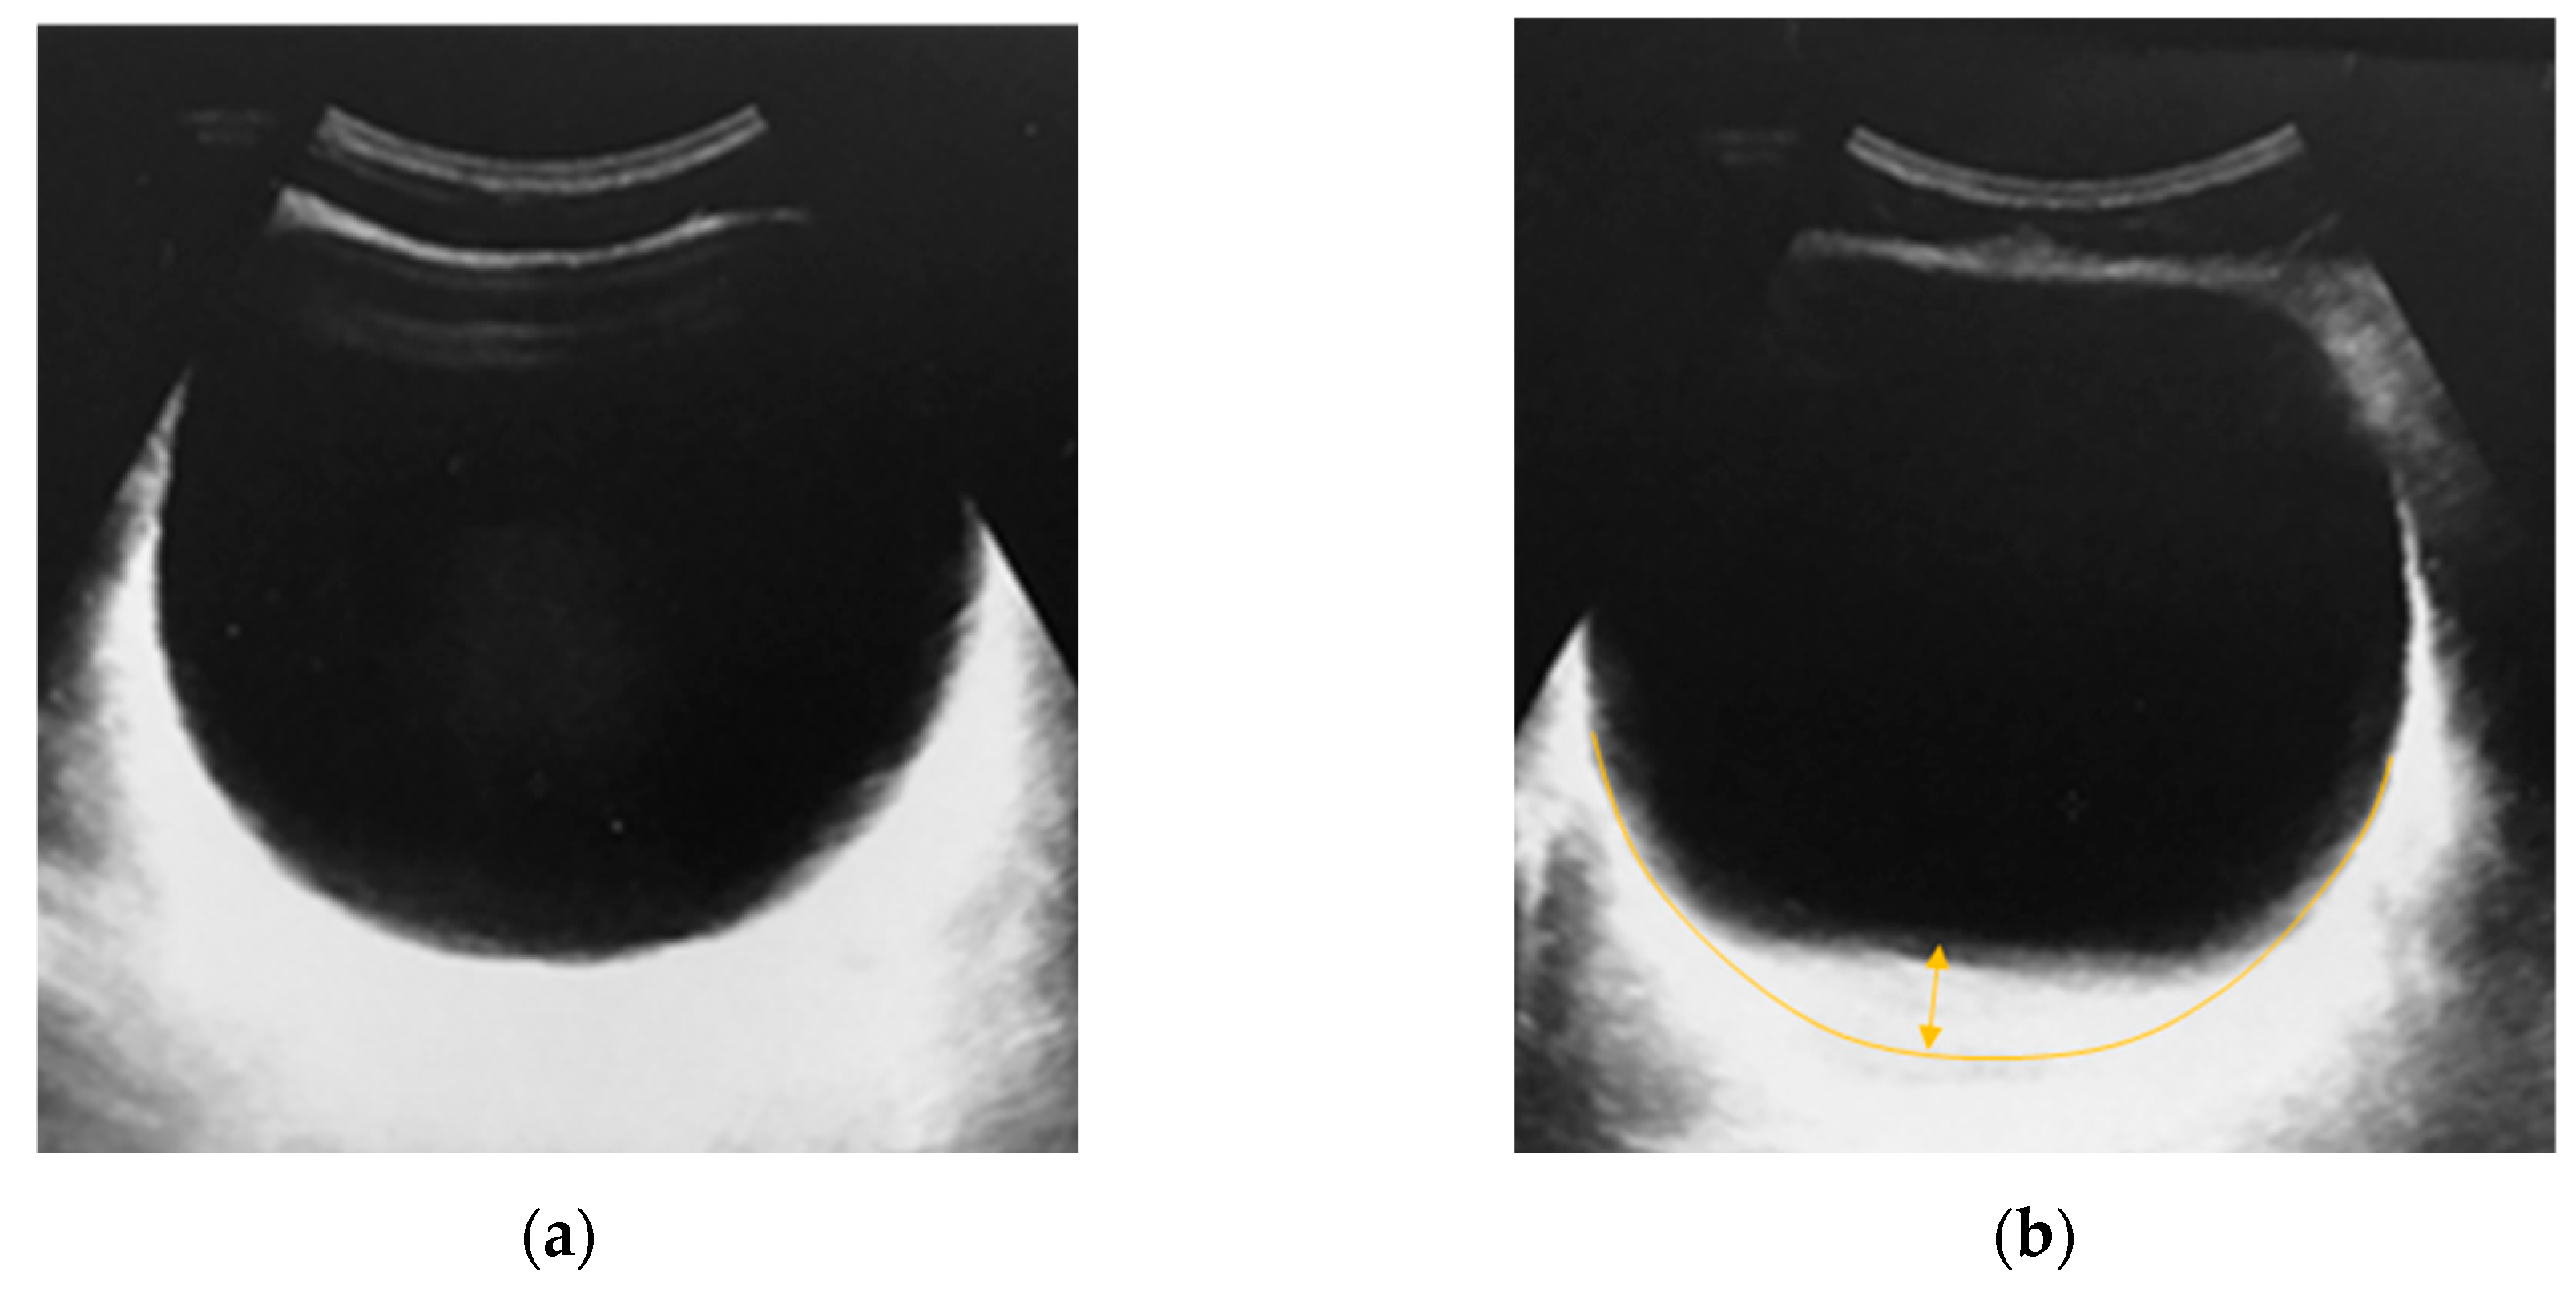

- Zhang, X.; Husmann, D.A.; Mynderse, L.A.; Alizad, A.; Fatemi, M. Non-invasive assessment of urinary bladder compliance using ultrasound: first validation study based on clinical urodynamic study. Annals of Translational Medicine 2021, 9(7), 547–555. [Google Scholar] [CrossRef] [PubMed]